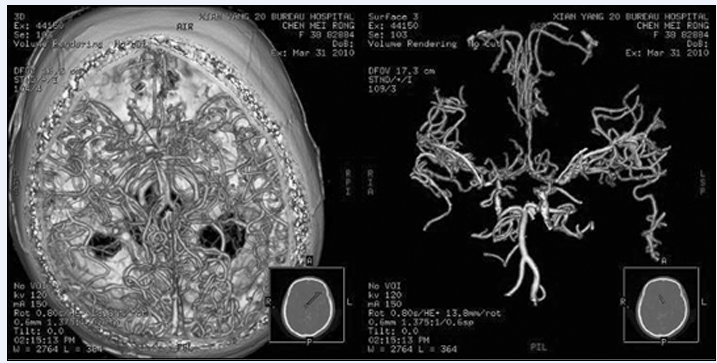

比较CTA和DSA在颅内动脉瘤的应用价值

脑血管病颅脑CTA与DSA的比较

3D-CTA及3D-DSA对颅内动脉瘤临床诊断价值